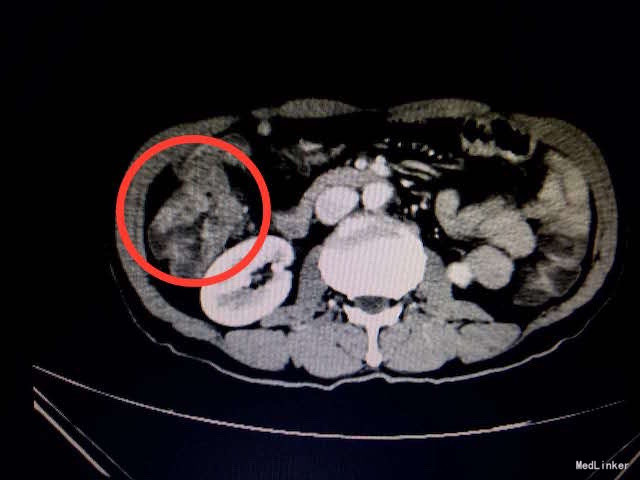

查体:消瘦体型,心肺查体阴性。腹软,右上腹深压痛,无反跳痛,未触及包块,肠鸣音正常。 辅助检查:入院血常规、生化、肝肾功、凝血、传染病未见明显异常。胃肠肿瘤指标正常。大便隐血试验(+)。腹部CT结果:结肠肝曲肠壁局部明显增厚,增强扫描强化明显,考虑恶性肿瘤,累及浆膜层(如下图所示)。